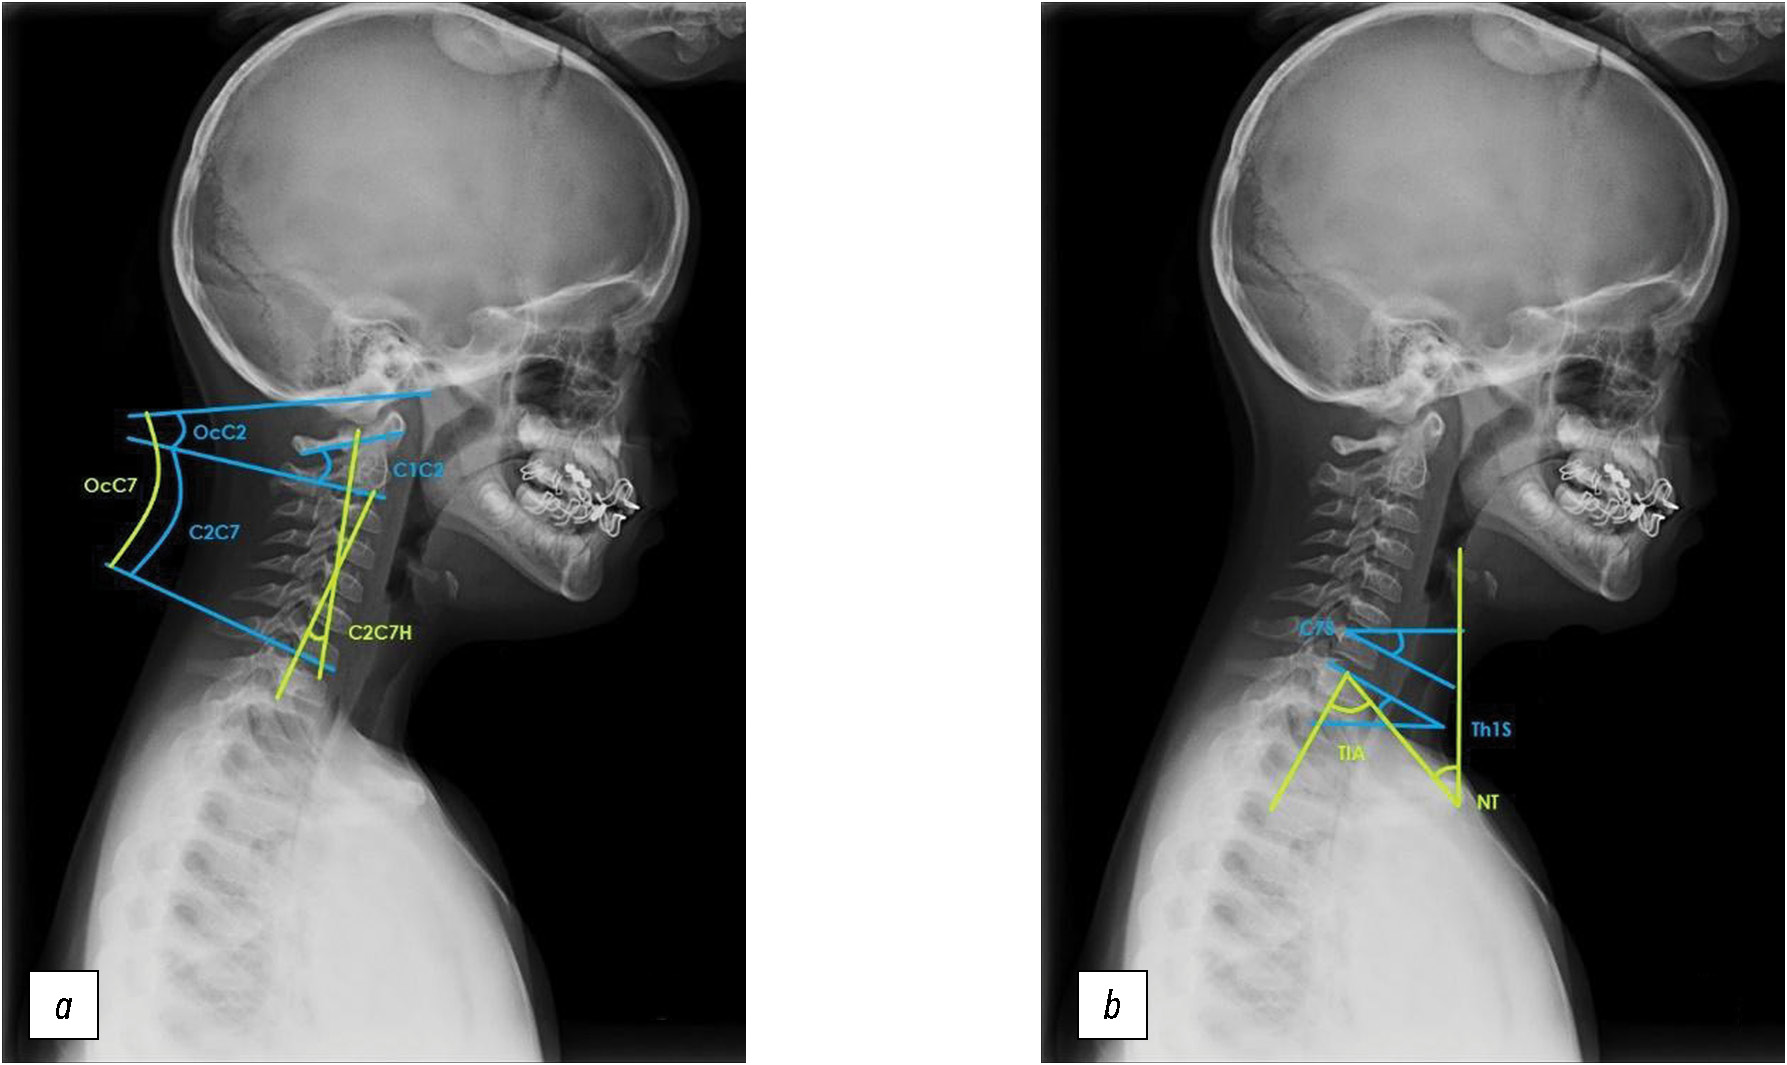

Assessment of target indicators

Based on X-ray data, the angular parameters of the cervical sagittal balance, most frequently mentioned in the literature, assessed by the Cobb method (Oc–C2, Oc–C7, C1–C2, C2–C7, C2–C7H, C7S, Th1S, TIA, and NT), were calculated [3, 5]. The method of calculating these parameters is presented in Fig. 1.

Fig. 1. a, b — technique for measuring cervical sagittal balance parameters.